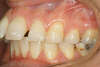

Décalage traité par gouttières

Fin de traitement